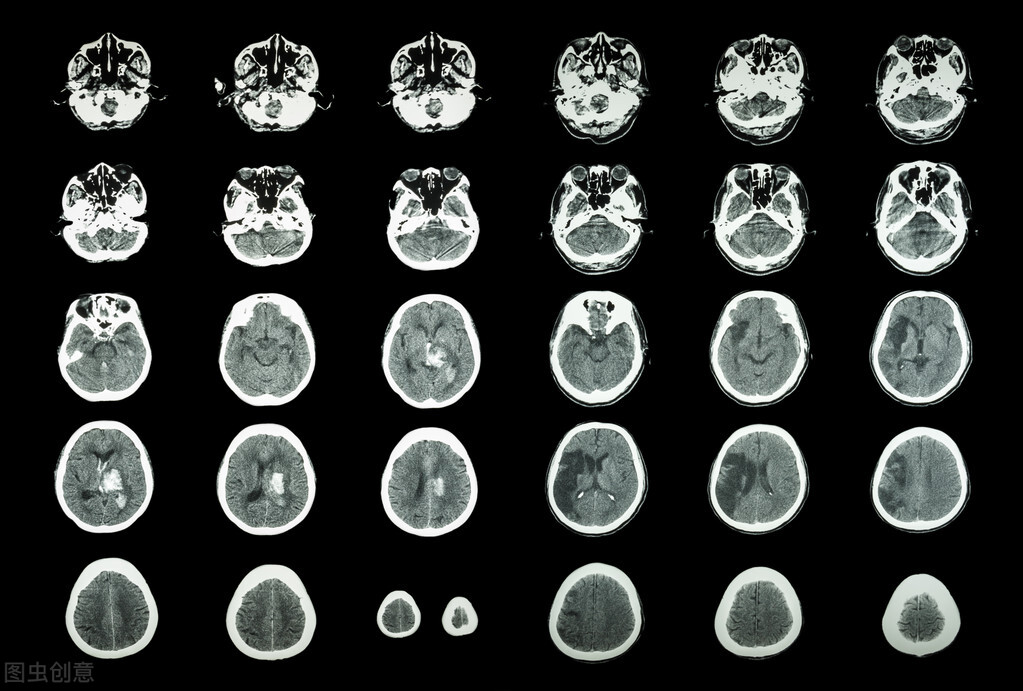

脑卒中是指由于血管原因引起的中枢神经系统(CNS)急性局灶性损伤所致的神经功能缺损,包括脑梗死、脑出血(ICH)和蛛网膜下腔出血。它是世界上导致死亡和残疾的第二大原因,也是导致痴呆和抑郁的主要原因。

根据其病因可分为缺血性(87%)或出血性(13%) 。其中,缺血性脑卒中是由脑动脉闭塞引起的,其原因可能是血栓性或动脉粥样硬化(50%)、栓塞性(25%)和微动脉闭塞(腔隙性卒中或梗死)(25%);出血性脑卒中主要由血管或动脉瘤的自发破裂或继发性外伤引起。